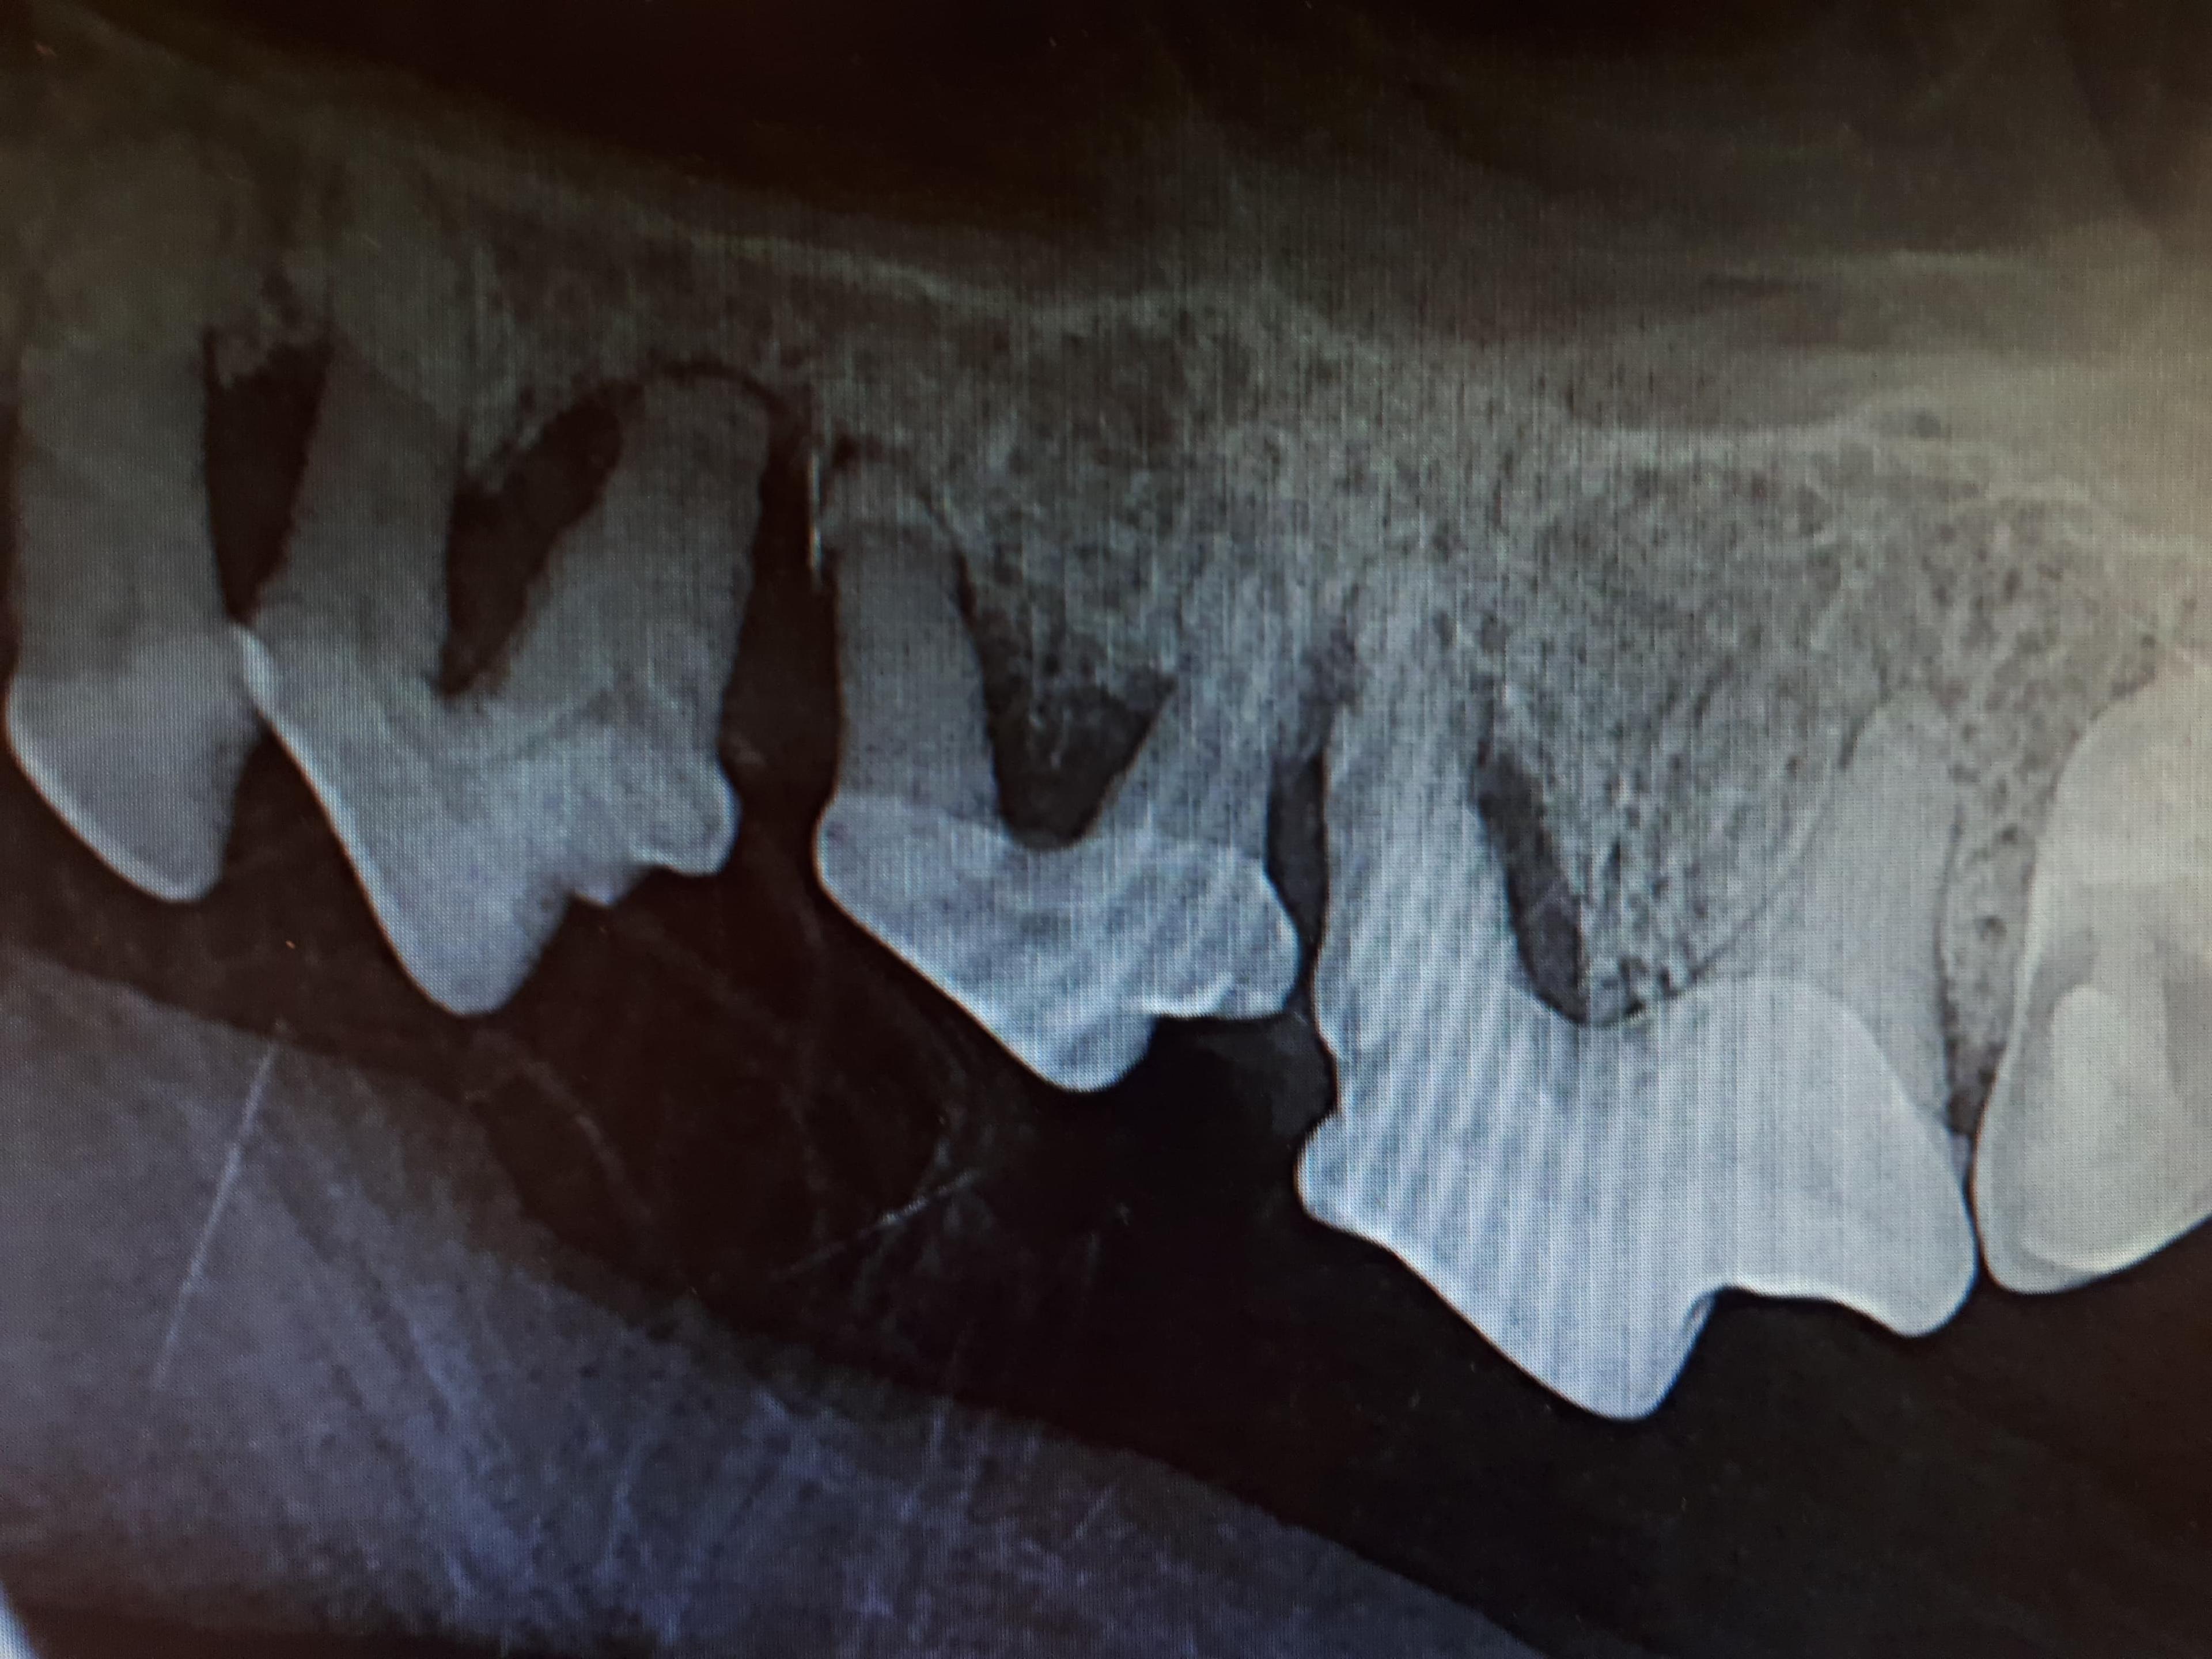

Diagnosen stilles vanligvis gjennom en grundig munnundersøkelse, som inkluderer kontroll av tannkjøtt, tenner og eventuelle infeksjoner. Røntgenbilder kan også tas for å vurdere tilstanden til kjevebenet og bekrefte hvor dypt infeksjonen har gått.